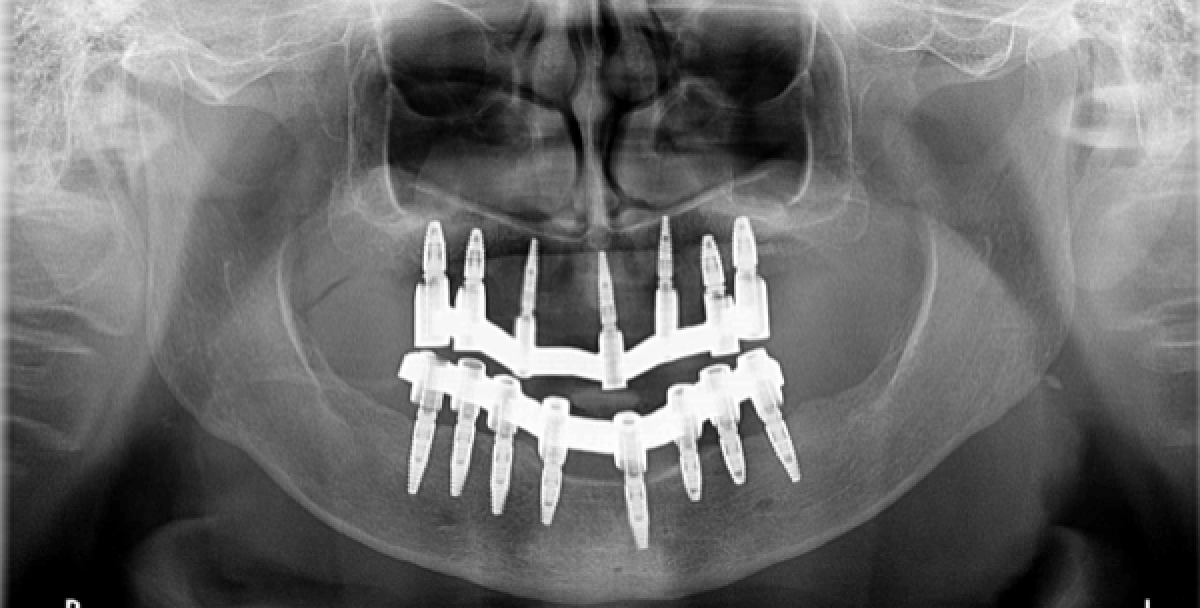

Once CT scan is viewed it was possible to establish the treatment plan that provides, first of all, the rehabilitation of the vertical height through the insertion of a temporary upper and lower prosthesis anchored to the elements still present in the arch, less compromised, elements 12 and 11 will be extracted. Then the bone graft will be performed in the upper arch, with large bilateral maxillary sinus elevation. Subsequently, after removal of the remaining teeth, 7 implants will be placed in the upper jaw and 8 in the lower jaw with immediate loading in guided surgery.

The second surgical phase involves, therefore, the remaining teeth extraction in the upper and lower arch, the positioning of the implant surgical guide and the insertion of 7 implants and 4 mini implants in the upper arch and 8 implants in the lower arch.

In both arches an immediate load is realized; in the upper arch in particular, however, this is possible by using the mini implants, as the quality of the bone did not allow for primary stability and sufficient torque (35N) to load the implants. Therefore, we will wait 4-6 months and then perform a traditional loading. (PICTURE 4)